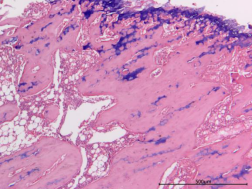

正常組、骨折組

圖1 HE染色圖 40X

樣本中細(xì)胞核被蘇木精染成藍(lán)色;細(xì)胞質(zhì)被伊紅染成深淺不同的粉紅色至深紅色。